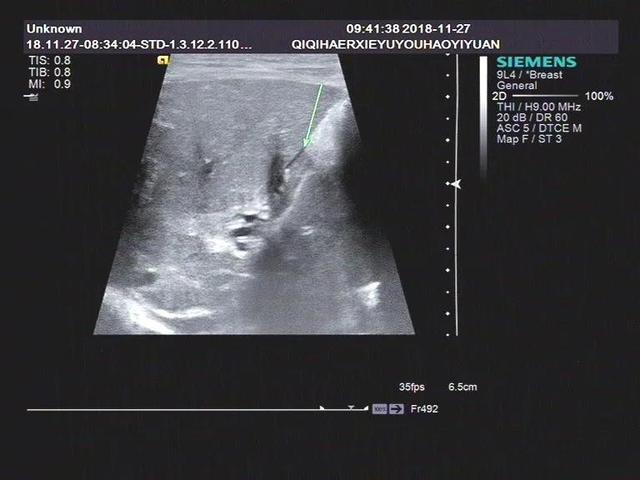

案例2

三是均伴有不同程度的肝脾肿大。早期肝脏回声普遍增厚增强,中晚期可见肝纤维化和肝硬化样声像图表现。

1.超声显示无胆囊型:肝门部形成的高回声形态各异,呈条索状高回声,无胆管扩张。

胆囊的声像图特征主要是:饥饿和餐后状态(建议喂奶后0.5小时观察,1小时多次观察),胆囊形态较小或假腔仅为狭缝状液体暗区。胆囊切面形态异常不规则,壁粗糙僵硬,部分病例可见双侧回声,进食后胆囊大小不变。